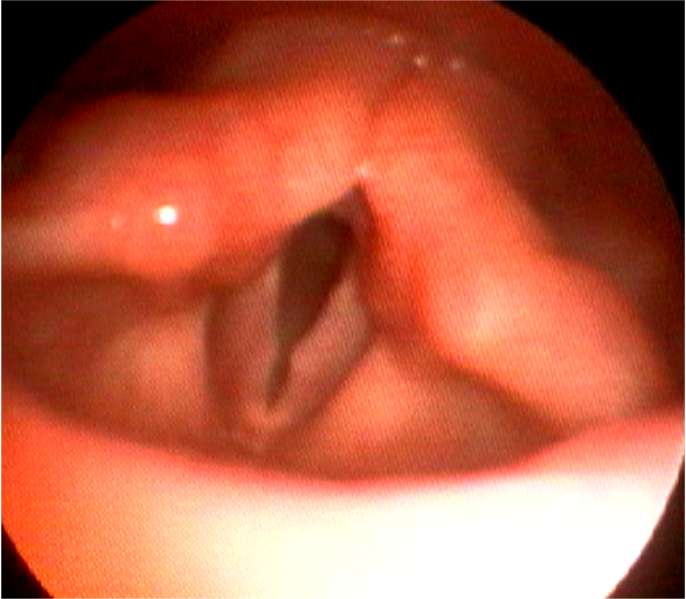

・声帯ポリープは声帯結節、声帯ポリープ、ポリープ様声帯の3種類にわけられます。

・声帯結節は声帯の前方1/3に両側性にできることが多く、小児では大声で話す男子によくみられ、成人では女性に多く発生します。

・声帯ポリープは成人の男女にみられ、通常、片側性で声を酷使する職業の人に発生します。

声帯結節

謡人結節